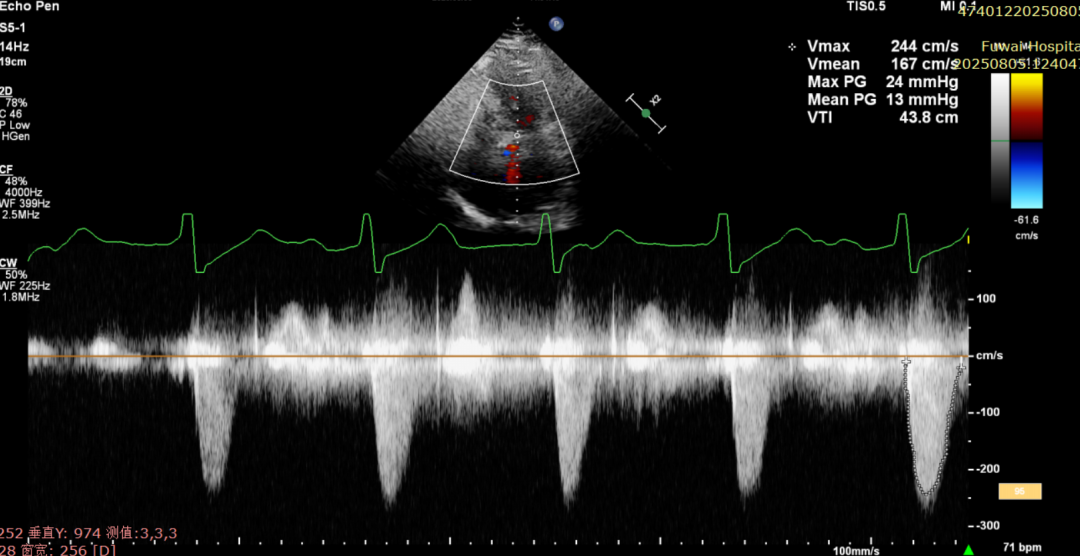

脱钩后输送器部分回收,瓣膜无位移及形变,确认瓣膜完全脱钩,回撤输送系统及导丝,超声再次评估,瓣膜位置及形态良好,无明显瓣周漏,峰值流速2.44m/s,平均压差13mmHg,患者未诉不适,入路缝合后返回病房